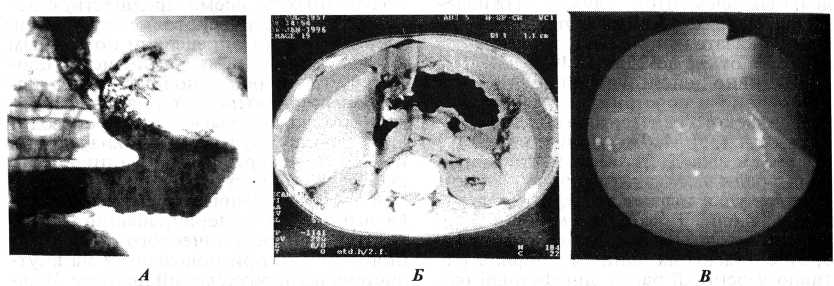

Рис. 1. Больная К., 56 лет. Эндофитный рак верхней трети тела желудка. А — рентгенограмма желудка (двойное контрастирование): ригидность стенок желудка в субкардиальном отделе с переходом на заднюю стенку и большую кривизну. Б — РКТ: в субкардиальном отделе определяется ограниченное кратное утолщение стенки желудка до 1,3 см, ригидность. В — эндофотография: в верхней трети тела желудка определяется некоторая неровность, ригидность слизистой оболочки.